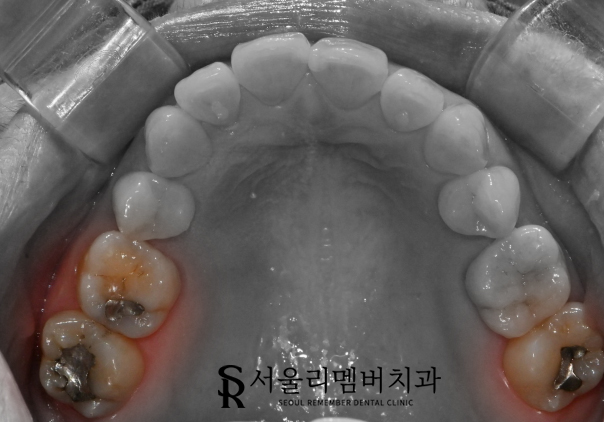

이게 무엇일까요?

구강 내에 어두운색의 인레이가 올려져 있는 모습인데요.

음 딱 보자마자 이곳들이 의심스러웠습니다.

기존 보철 제작에 사용된 재료는 '아말감'이었는데요.

예전에는 저렴한 비용으로 많은 분들이 선호했던 재료지만,

요즘에는 환경, 건강 문제로 인해 거의 사용하지 않고 있습니다.

꽤 오랜 시간이 흘렀다는 것을 눈치챌 수 있었죠.